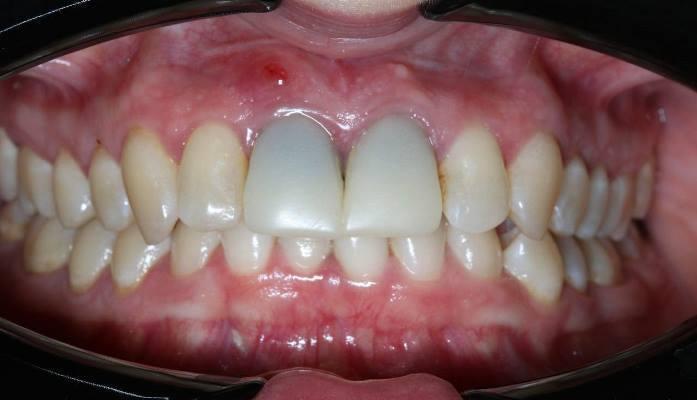

Фото 1.

По рекомендации своего супруга она обратилась в нашу клинику. Действительно, анатомическое расположение зубов таково, что после их удаления образуется большой горизонтальный костный дефект. Будет дефицит костной ткани.